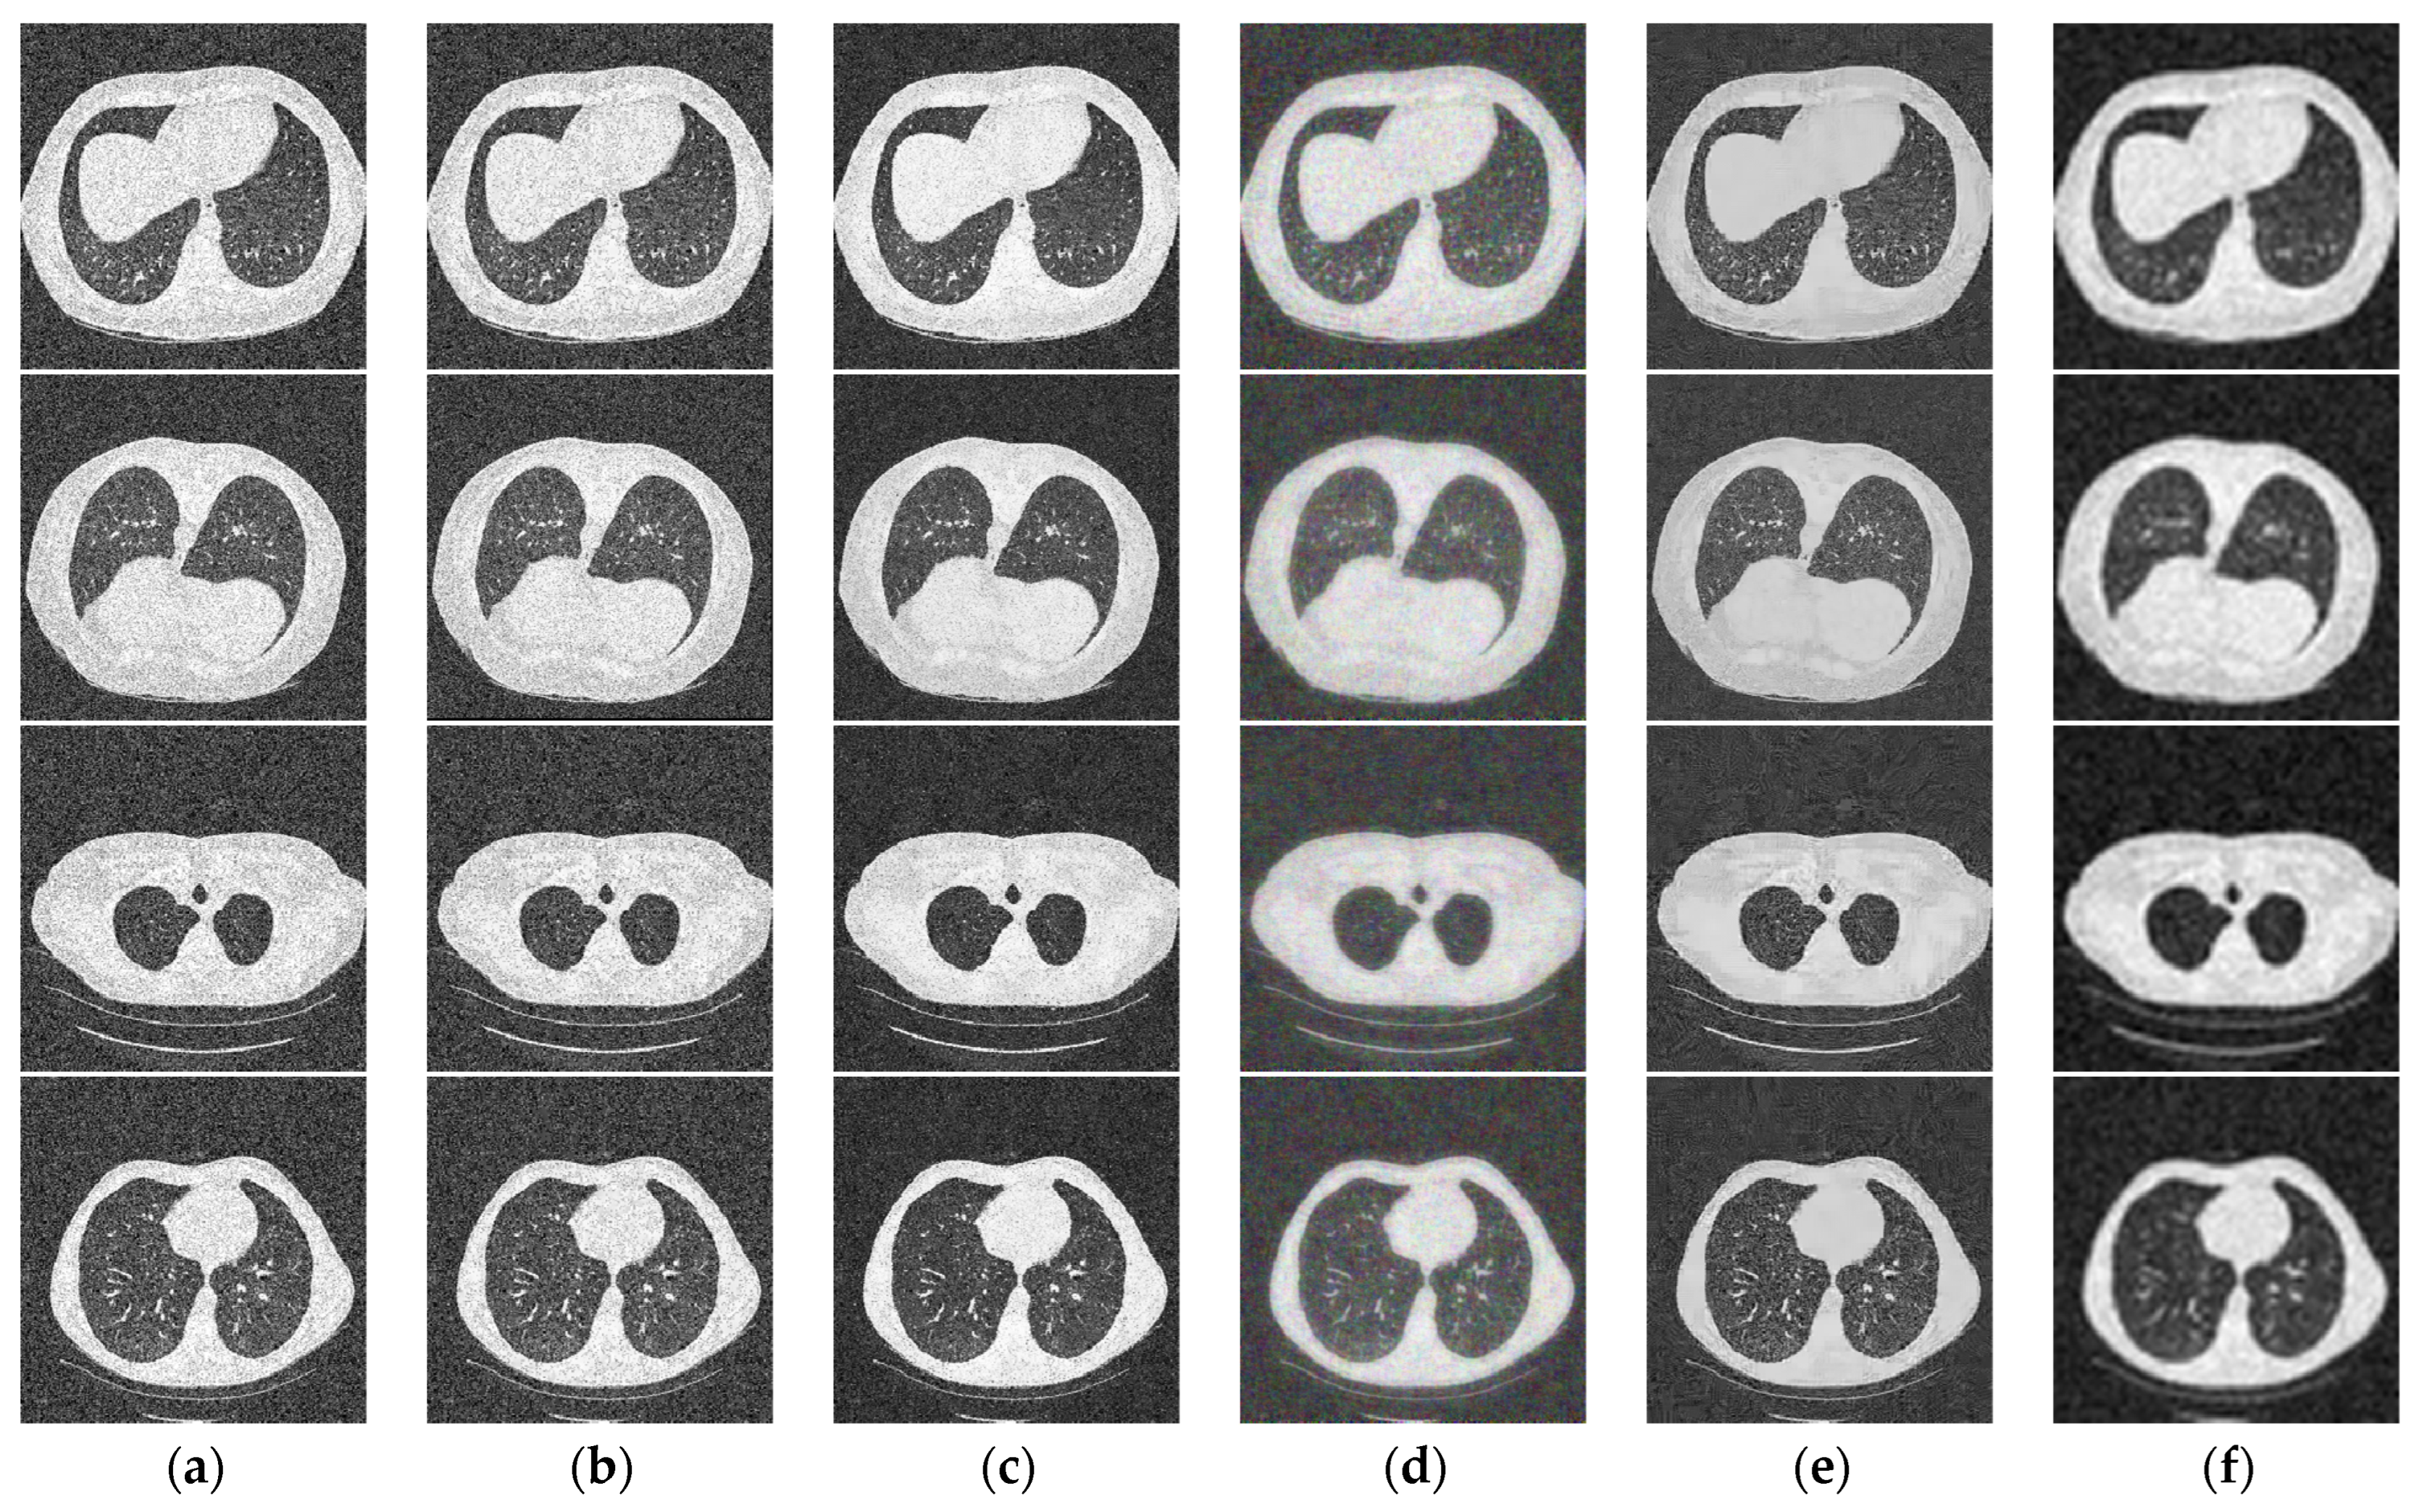

| Image | I1 | I2 | I3 | I4 | ||||

|---|---|---|---|---|---|---|---|---|

| Metrics | PSNR | SSIM | PSNR | SSIM | PSNR | SSIM | PSNR | SSIM |

| AD | 18.48 | 0.2964 | 18.38 | 0.2407 | 18.42 | 0.2352 | 18.27 | 0.3298 |

| BF | 20.37 | 0.3593 | 19.95 | 0.3004 | 20.21 | 0.2965 | 19.71 | 0.3731 |

| KSVD | 22.61 | 0.5578 | 22.49 | 0.3787 | 23.34 | 0.5512 | 22.67 | 0.5660 |

| BM3D | 20.66 | 0.5479 | 23.63 | 0.5736 | 22.80 | 0.4603 | 21.15 | 0.4830 |

| W-NMM | 22.67 | 0.6219 | 24.20 | 0.6798 | 23.62 | 0.6557 | 22.43 | 0.6714 |